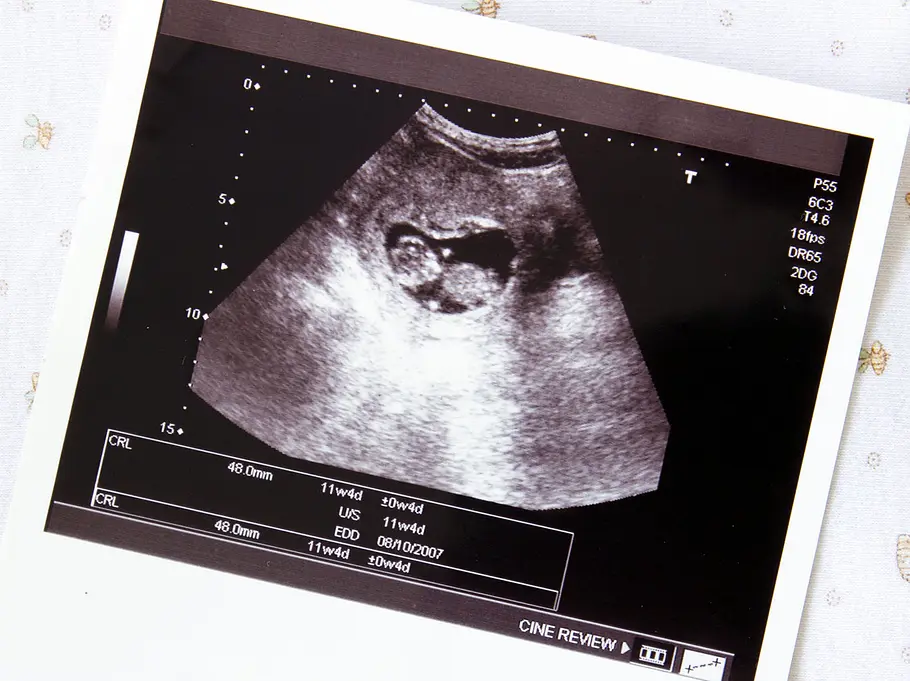

Schon kurz nach dem Ausbleiben der Regel kann durch einen Test festgestellt werden, dass eine Frau schwanger ist. Auf dem Ultraschall ist zu diesem Zeitpunkt noch nichts sichtbar. Weder die Frau noch ein Arzt können ganz zu Beginn mit Sicherheit sagen, ob sich eine intakte Schwangerschaft entwickeln wird. Frühestens zwei Wochen nach Ausbleiben der Regel kann im Ultraschall gesehen werden, ob das Herzchen schlägt. Auch der sichere Ausschluss einer Eileiterschwangerschaft ist vorher nicht möglich. Aber natürlich ist bei allen Frauen, die sich auf ein Kind freuen, schon mit dem positiven Test die Hoffnung geboren, dass sie in neun Monaten ein rosiges Baby in den Armen halten werden.

Leider sind die Momente nicht selten, in denen Frauenärzte ihren Patientinnen mitteilen müssen, dass sich die Schwangerschaft nicht normal entwickelt oder sie eine Fehlgeburt haben. Und oft kommt es überraschend. „Manchmal kommt eine Schwangere. Denkt, dass alles gut ist. Und wenn ich dann kein klopfendes Herz sehe, ist das für beide dramatisch“, berichtet Eder. Dafür die richtigen Worte zu finden, sei jedes Mal schwer. „Ein fürchterlicher Moment.“ Und ihr ist klar, dass es jetzt keinen Trost gibt. Denn sie weiß aus beiden Perspektiven, wovon sie redet.

Die Gynäkologin erklärt, dass fast immer zeitnah eine Ausschabung gemacht wird. „Außer, man hat im Ultraschall noch nichts gesehen. Man kann jedoch unter Umständen auf eine Ausschabung verzichten, auch wenn man schon etwas sah. Aber je weiter es sich der zwölften Schwangerschaftswoche genähert hat, desto länger und kräftiger kann dann die Blutung sein. Das erfordert den engen Kontakt zur Patientin um zu hören, wie es ihr geht und Probleme wie Eisenmangel im Blick zu haben. Aber ab der zwölften Schwangerschaftswoche ist da schon einiges Gewebe, das raus muss. Da ist eine Ausschabung wirklich sinnvoll. Doch manche Frauen wollen das einfach nicht. Aus ganz individuellen Gründen.“